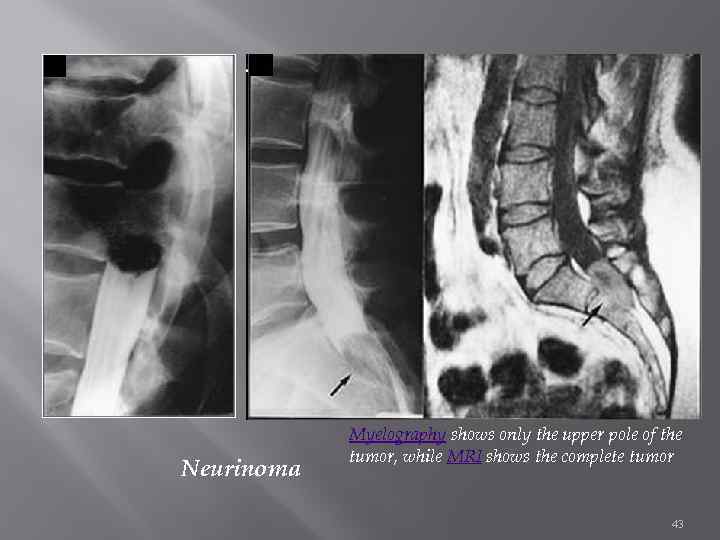

Миелография нисходящая и восходящая Нисходящая липоидол, майодил субокципитальная пункция сидящему больному спускаясь вниз, останавливается над патологическим процессом блокирующим ликворные пути опухоль, выпавший фрагмент диска Восходящая газ: кислород или воздух, легкие рентгеноконтрастн вещества При ЛР поднимается вверх, останавливается под патологическим очагом, блокирующим ликворные пути Противопоказание опухоль краниоспинальной локализации 42

Neurinoma Myelography shows only the upper pole of the tumor, while MRI shows the complete tumor 43